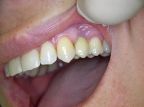

Ein besonderer positiver Effekt der Implantate ist, dass sie den Kieferknochen und das Zahnfleisch erhalten, während sich der Knochen unter Brücken und Prothesen hingegen abbaut. In vielen Fällen lässt sich so die natürliche Rot-Weiß-Ästhetik, also das harmonische Zusammenspiel von Zahnfleisch und Zähnen erhalten, so dass implantat-getragene Kronen kaum von eigenen gesunden Zähnen zu unterscheiden sind.

So können Lücken geschlossen werden, ohne dass gesunde Nachbarzähne beschliffen werden müssen und unnötig Zahnsubstanz abgetragen wird (Brückenversorgung).